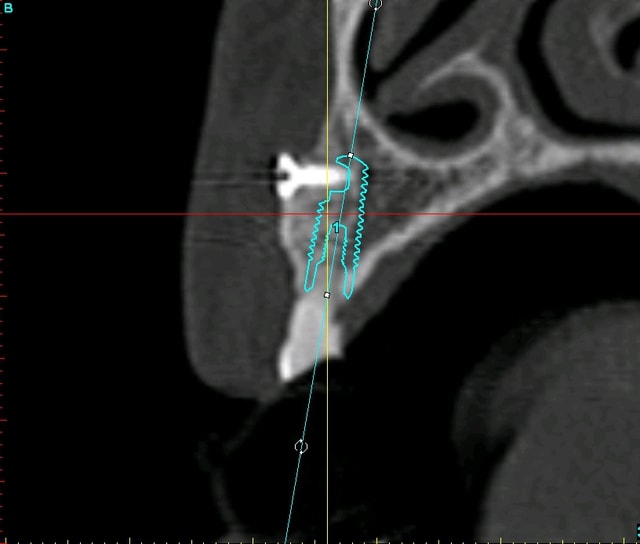

je vous remets les images avant/après pour un comparo...;-)

Planif euc3aq - Eugenol

Plan c8bcsp - Eugenol

Au fait tu utilises quoi comme logiciel de planification 3D...Le cone beam ainsi que tes images 3d sont très belles....Et c'est vrai que t'as pas des mains de maçon...;-)